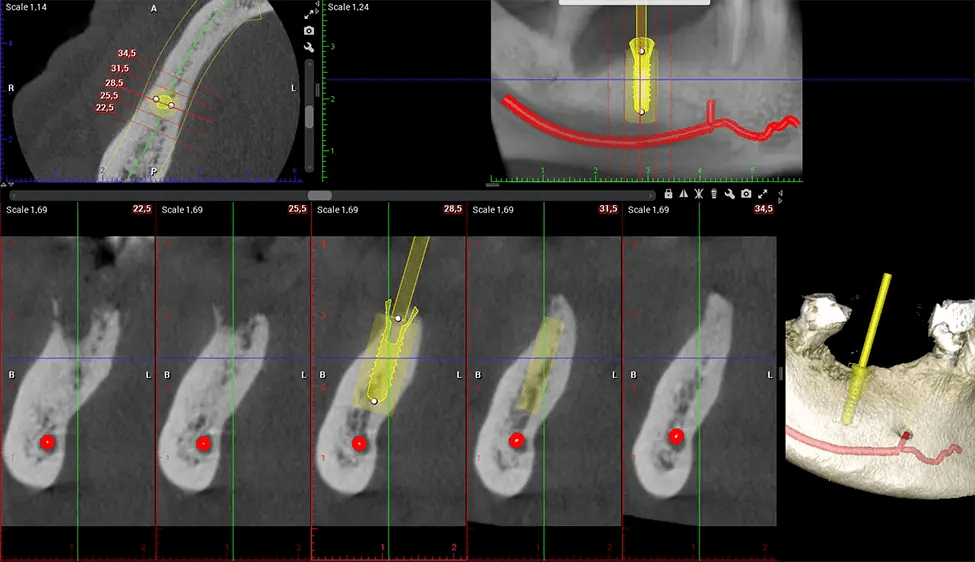

When paired with extractions, dental implant placement, or bone grafting, CBCT technology can provide you with a quicker and much more comfortable experience. This is because the 3D image provides a more detailed picture of your entire oral cavity, allowing your dentist to walk you through each step of the process before it occurs. This often helps patients feel more prepared and comfortable overall, especially if they have had a traumatic experience with past dental treatments.

After the scanning process, the captured X-ray images are processed by the CBCT software, which applies algorithms to reconstruct a detailed 3D image of the scanned area. The software compiles these individual X-ray images and creates a digital 3D representation of the patient’s anatomy. The reconstructed 3D CBCT image can be viewed and analyzed by the dentist or radiologist. This image can be manipulated, rotated, and zoomed in or out to examine specific structures and evaluate the patient’s condition.

Planmeca Viso G7 CBCT ( Cone Beam CT Scan ) is designed to surpass the demands of industry leaders, specialists, and large institutions. It’s has a large ø25×30 cm sensor with four built-in cameras. It can capture unlimited volume sizes from a ø3×3 cm to a ø30x30cm volume capturing the skullcap through C7 on the cervical spine. The Planmeca Viso G7 offers the industry’s largest single volume scan of ø30×19 cm. It’s poised to handle advanced imaging modalities such as Planmeca ProFace® and Planmeca 4D™ Jaw Motion technology. The occipital head support allows an unimpeded view of facial tissue.

Our patented SCARA technology enables doctors to capture True Extraoral Bitewings that are as accurate at detecting caries as a 2D bitewing series, but with half the radiation dose. With our bitewings, doctors can view the apices of teeth on both jaws providing a more comprehensive view of the patients’ anatomy.